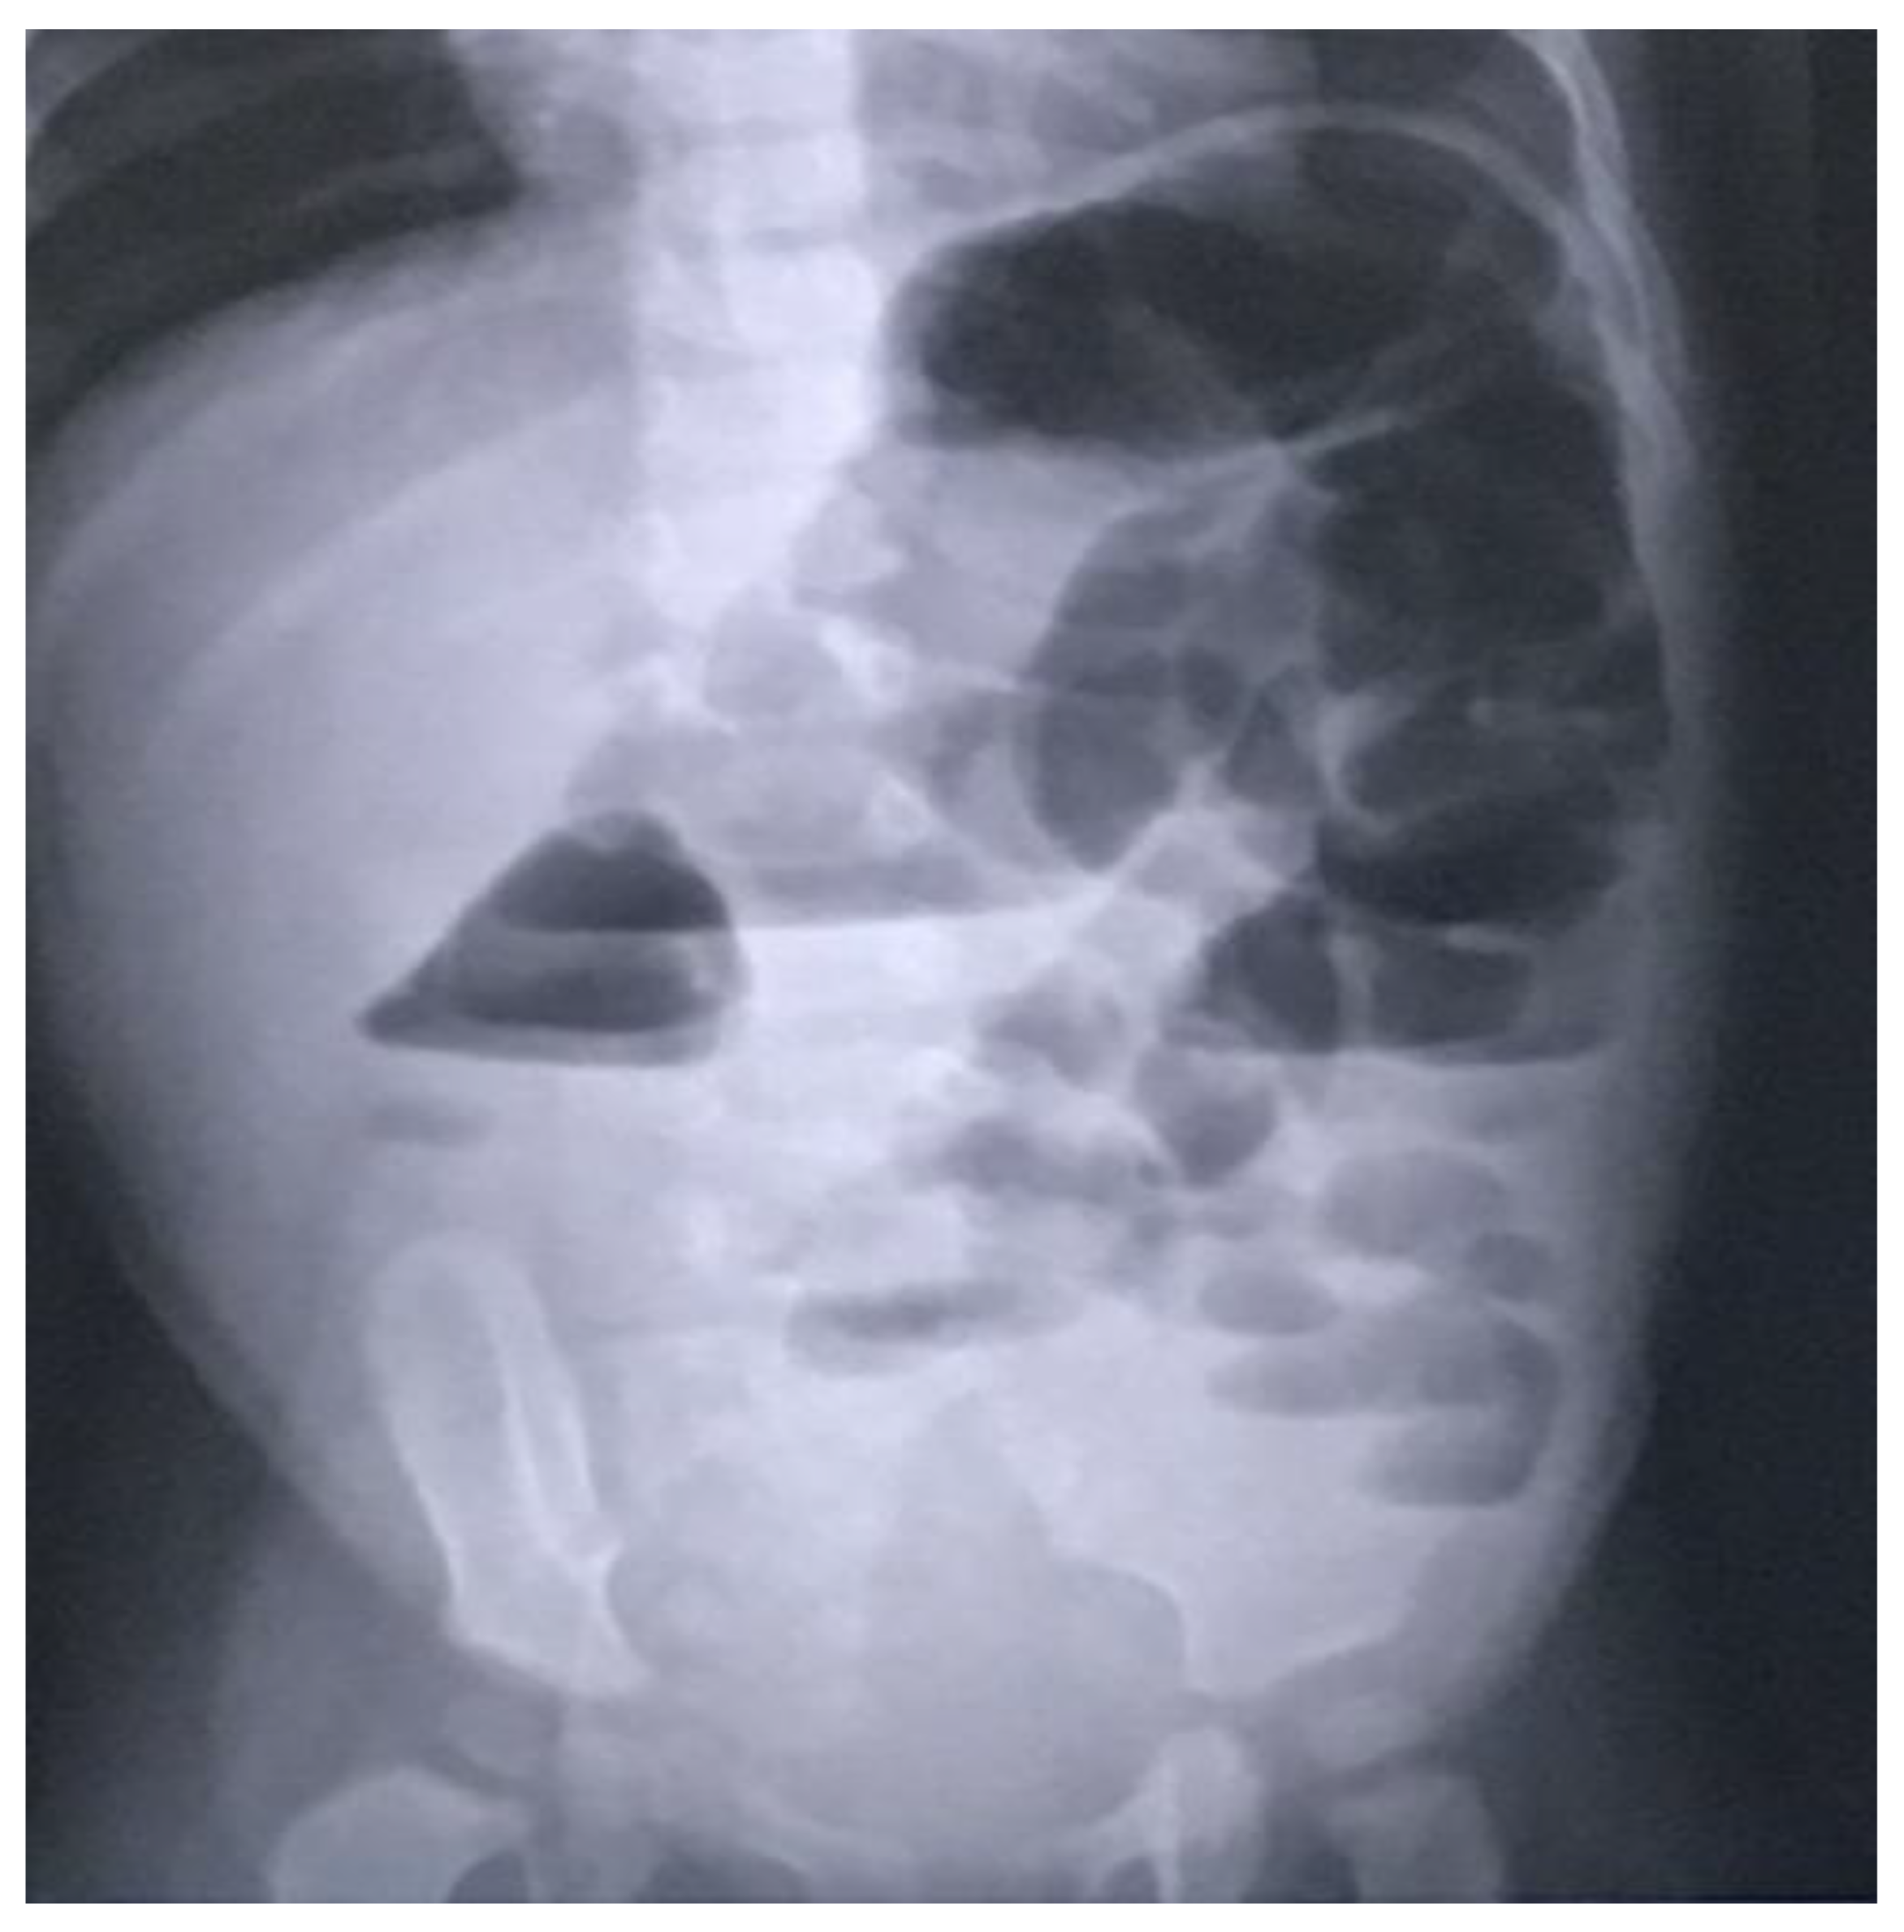

In light of the ongoing significant abdominal distension, an abdominal X-ray was conducted, revealing bowel dilation characterized by air-fluid levels and the absence of any luminal obstructive lesion (Figure 1).

Figure 1.

Radiographic indications of bowel distension with discernible air-fluid levels and the nonexistence of any lesion causing luminal occlusion.